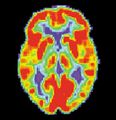

مسح PET لمخ غير مصاب - الصورة مقدمة من مركز الإحالة والتوعية بمرض ألزايمر التابع للمعهد الوطني للشيخوخة بالولايات المتحدة.

مسح PET لمخ مصاب بمرض ألزايمر - الصورة مقدمة من مركز الإحالة والتوعية بمرض ألزايمر التابع للمعهد الوطني للشيخوخة بالولايات المتحدة.

مرض ألزايمر هو مرض تنكسي وقاتل يصيب المخ، حيث تُفقد الاتصالات الخلوية بخلايا المخ. يعتبر مرض ألزايمر من أكثر أنواع الخرف شيوعاً.[2] عالمياً، يصاب بمرض ألزايمر حوالي 1-5% من السكان.[3] تقع النساء بشكل غير متناسب ضحايا لمرض ألزايمر، مع وجود أدلة تشير إلى أن النساء المصابات بمرض ألزايمر يظهرن ضعفاً إدراكياً أكثر حدة مقارنة بالذكور المصابين بالمرض، بالإضافة إلى معدل أسرع من التدهور السلوكي.[4]